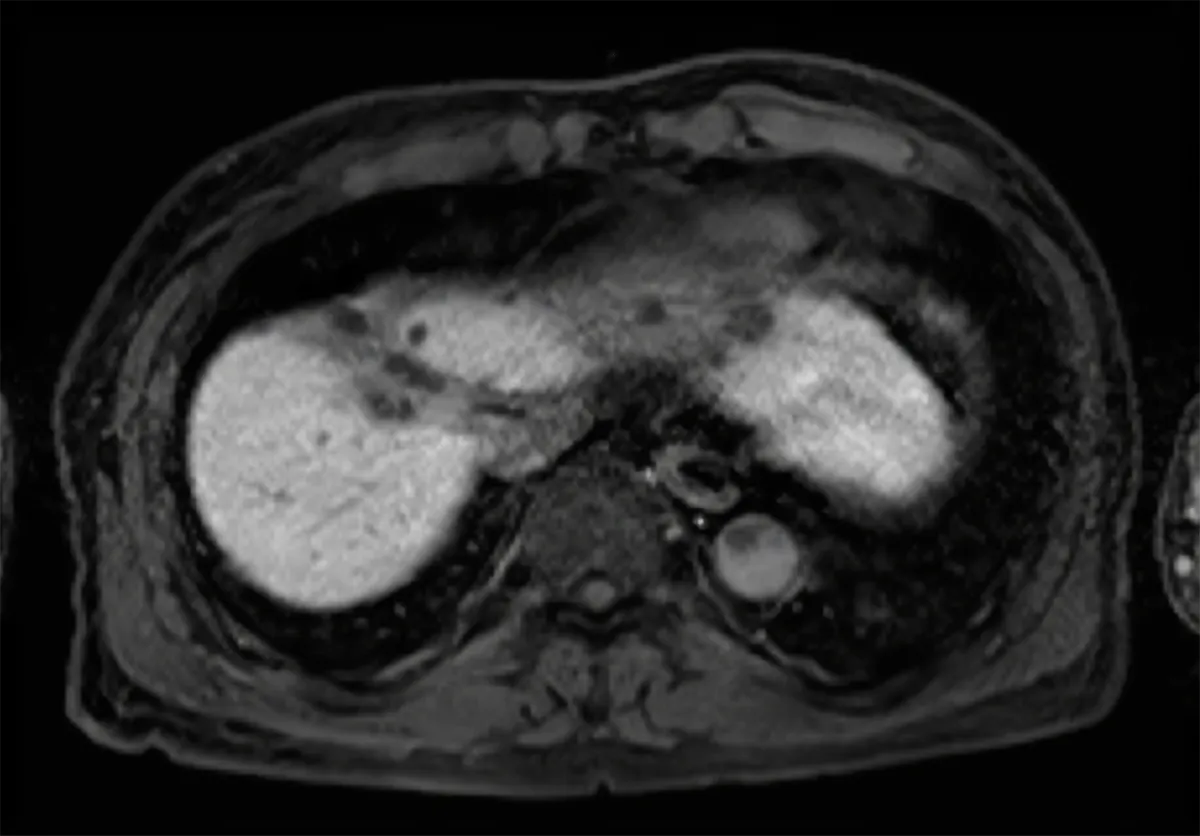

Primary liver cancer is the sixth most common cancer diagnosed worldwide. Fiducial markers can be used to guide both radiotherapy and ablation treatments. The implantation of traditional markers can, however, lead to bleeding, painful bile leakage and, for example in the case of colorectal metastases, to the spread of tumor cells (seeding).

Gold Anchor is suitable for percutaneous implantation in most soft tissue organs, e.g. liver, pancreas, kidney, adrenal gland, breast, oligomets in abdomen and inguinal metastases. At Karolinska the implantation of Gold Anchors in abdominal tumors are sometimes done by oncologists but in most cases the patient is referred to radiologists – every physician who take needle biopsies is skilled to implant Gold Anchor.

Gold Anchors are typically implanted percutaneously into abdominal organs. This x-ray video shows a 0.28×20 mm marker (GA200-20) implanted in liver while the patient breathes. This example illustrates the value of positioning soft tissue based on a fiducial marker rather than on distant bony anatomy.